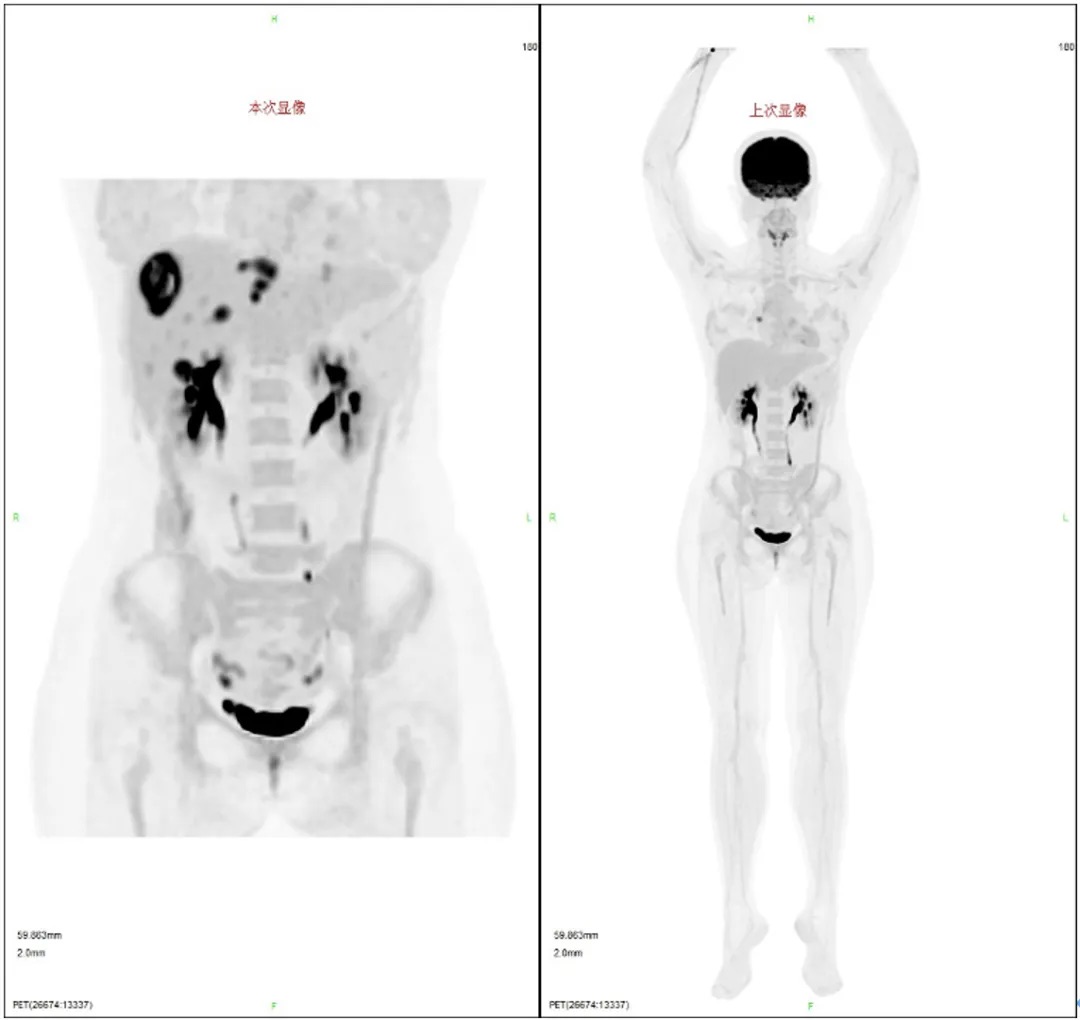

2023-12-18:复查CT提示肝S8包膜下新发病灶(图2),遂行超声引导下穿刺活检,病理提示DLBCL。考虑患者早期复发,综合评估病情后决定给予CAR-T(阿基仑赛)治疗。

2023-12-28:行单个核细胞采集后,予维泊妥珠单抗、利妥昔单抗、吉西他滨、地塞米松和顺铂方案(Pola-R-GDP)桥接治疗。2024-1-30腹部增强CT提示肝S8包膜下病灶较前增大。

疗效评估:回输后1个月和3个月PET-CT疗效评估均为完全缓解(CR)(图3)。

图2 CAR-T治疗前PET-CT检查;左侧为2023-12-18检查结果,提示肝S8包膜下新发病灶;右侧为R-DA-EPOCH和放疗治疗后的检查结果

图3 CAR-T回输后3个月的PET-CT,疗效评估为CR